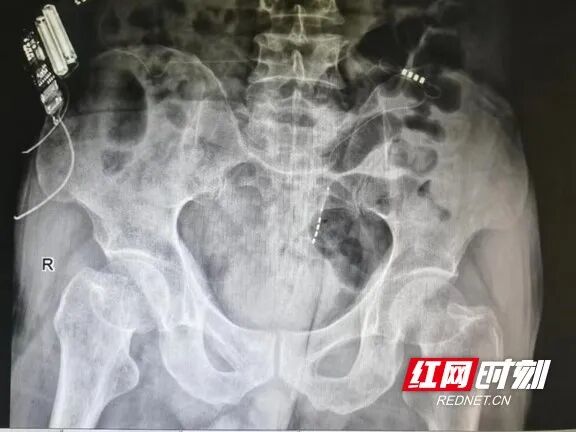

术后刺激器植入情况。